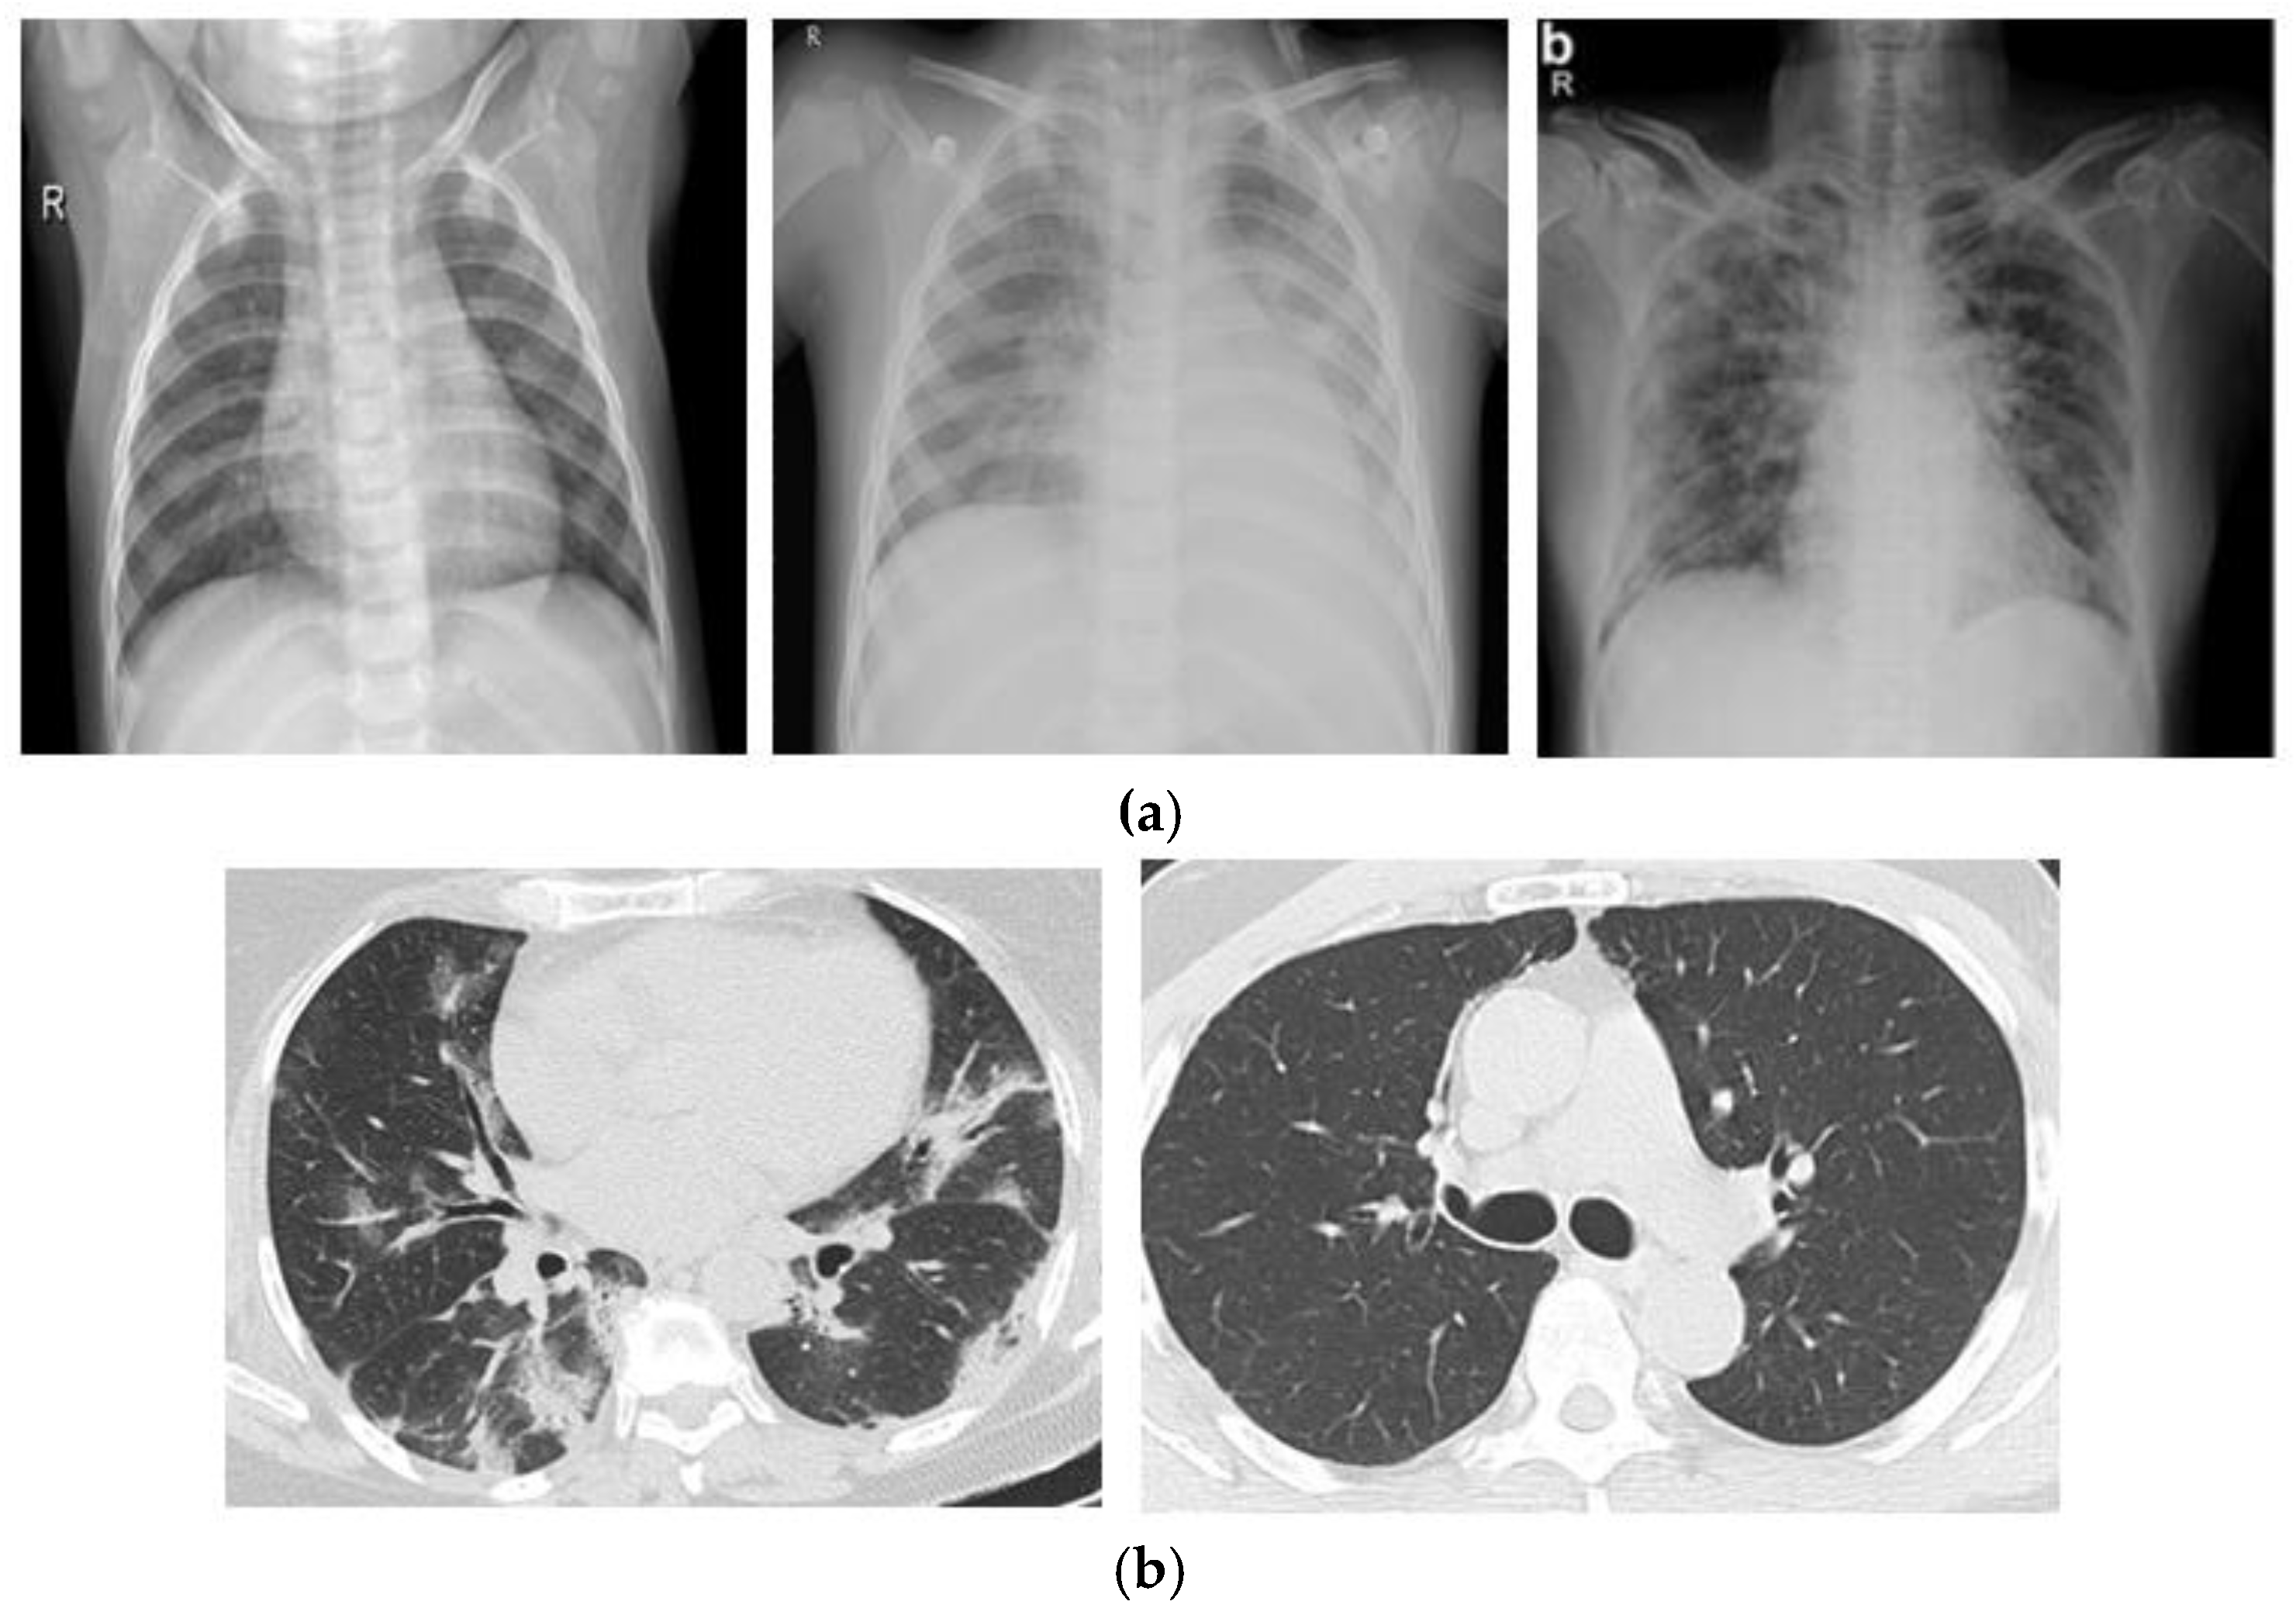

3.1. Dataset

3.2. Watershed Based Region Growing Segmentation